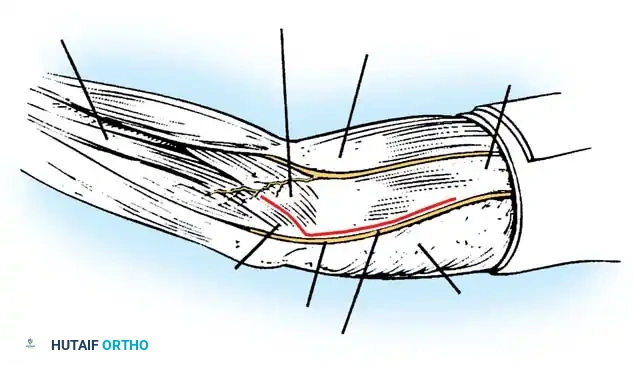

Make a generous posterior incision beginning in the midline 10 cm proximal to the olecranon. Continue distally to just proximal to the tip of the olecranon, curve slightly laterally over the lateral humeral condyle and radial head, and extend 5 cm distally onto the forearm. Undermine and retract the full-thickness fasciocutaneous flaps to expose the tendinous insertion and aponeurosis of the triceps muscle.

Ulnar Nerve Neurolysis

Before any deep dissection, locate the ulnar nerve proximally. Dissect it meticulously from its bed along the postcondylar groove of the medial epicondyle.

Careful isolation and vessel-loop control of the ulnar nerve are mandatory before addressing the medial joint capsule.

Triceps Flap and Subperiosteal Stripping

Beginning proximally, use sharp dissection to reflect the aponeurosis of the triceps distally, forming a robust tongue-like flap of tissue that remains attached to the olecranon.

Starting 7.5 cm proximal to the joint, make a midline incision through the underlying muscle fibers of the triceps down to the olecranon. Curve this deep incision around the lateral edge of the olecranon.

Fig. 58-26 Speed technique of open reduction. A, Incision and ulnar nerve isolation. B, Triceps aponeurosis reflected distally; subperiosteal stripping of muscles. C, Lateral view showing extent of mobilization. D, V-Y closure.

Subperiosteally free all muscle attachments from the distal humerus, both anteriorly and posteriorly.

Aggressive subperiosteal elevation is required to mobilize the distal humerus completely.

Release the attachments of the joint capsule and collateral ligaments around the humeral condyles. Mobilizing the tissues around the medial condyle and anterior humerus can be exceptionally difficult due to scarring, but complete mobilization of the distal humerus is non-negotiable for reduction.